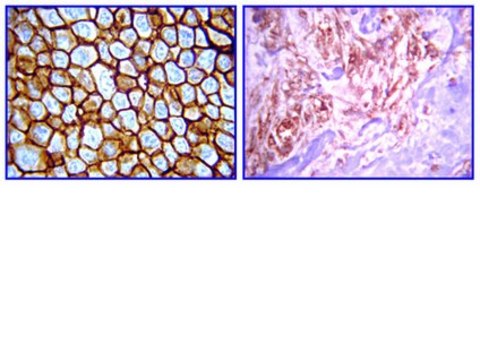

Immunohistochemistry(paraffin): Representative testing from a previous lot.

Optimal Staining of erbB-4/HER-4 Monoclonal Antibody: DCIS and Pancreatic Cancer